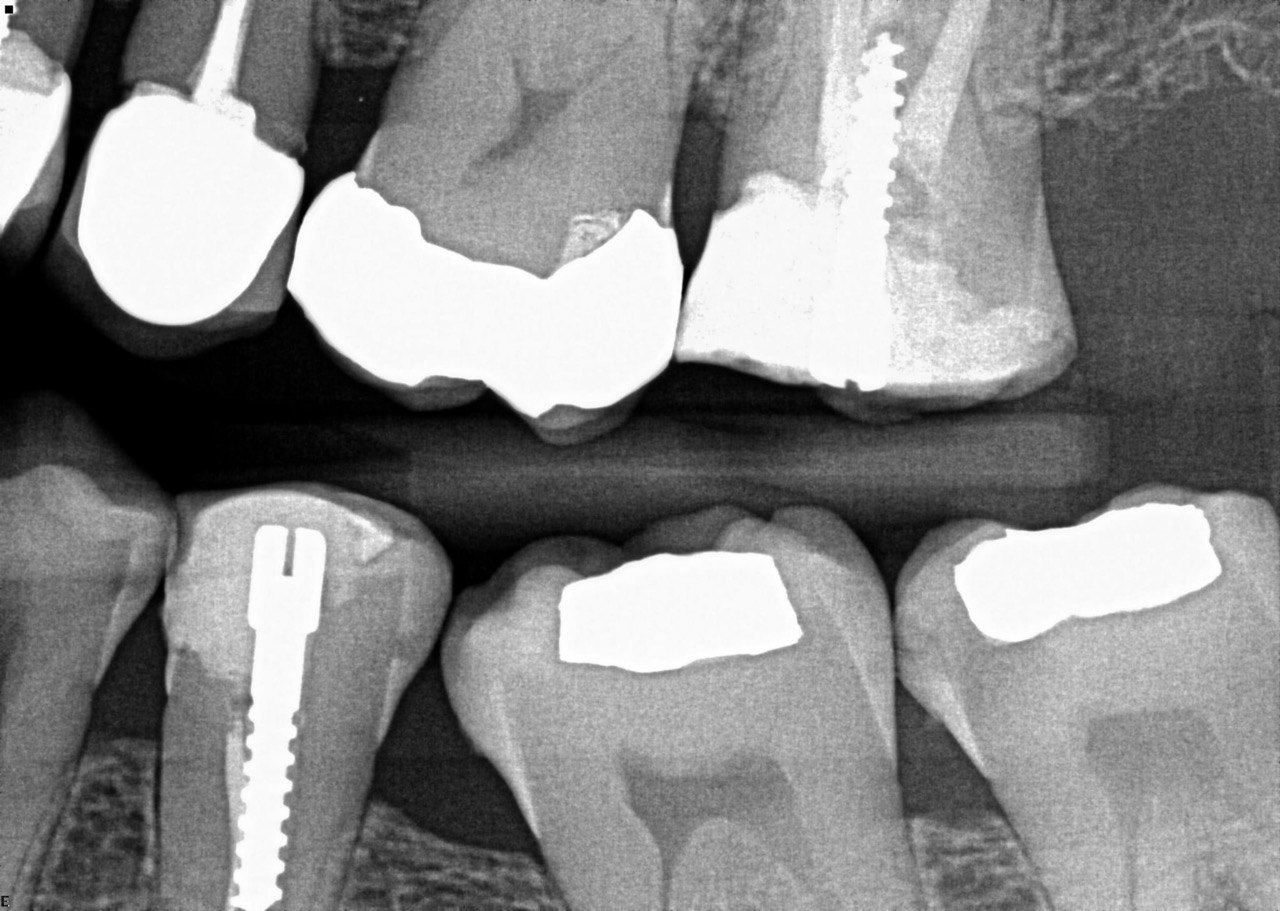

Question 1: What materials cannot be seen in the print of the X ray?

Question2: Which surface shows overhang?

Question 3: Which option is not evident on the print of the X ray?

Question 4: Which options cannot be seen in the print of the X ray?

Question 5: What options cannot be selected for tooth # 4.6?

Question 6: What options cannot be seen in the print of the X ray?

Question 7: What option cannot be identified on the print of the X ray?

Question 8: What condition can be seen in the X ray?

Question 9: Which option cannot be seen in the lower jaw?

Question 10: Which option can be selected for the following X ray?